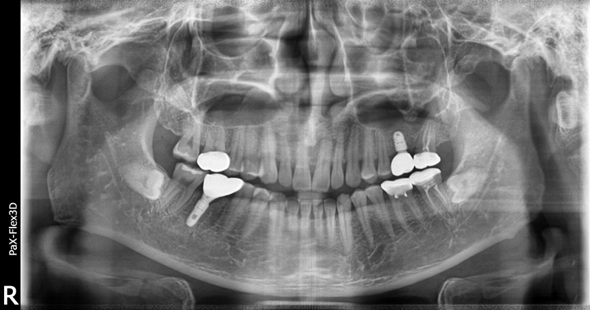

68세 남성

보험임플란트

(전) 2021-11-05 (후) 2022-08-18

만 65세 이상으로 국가에서 금액을 일부 지원하는 보험임플란트를 진행하신 환자분입니다.

치아가 상당 부분 결손되어 있어 생활하시는데 불편함이 많으셨을텐데, 임플란트 시술 후 씹는 즐거움을 되찾을 수 있었습니다.

상실된 치아를 방치하게 되면 치아가 조금씩 이동해 치아 배열이 망가지고 임플란트 식립이 어려워질 수도 있습니다.

따라서 빠르게 치과에 방문하셔서 치료받으시는 것이 가장 좋습니다.